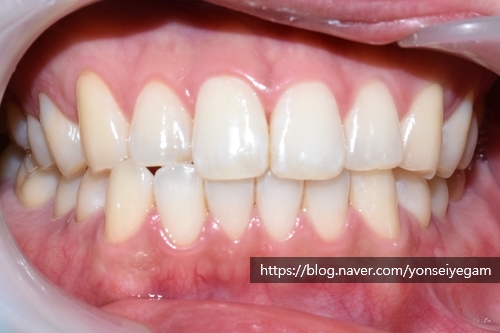

아래는 첫 날 치료(스케일링, 치아패인곳 떼우기, 원데이2회미백 진행)의 전&후 사진입니다.

같은 날 치료 전 후 다시 비교해 볼게요

당일 스케일링,화살표패인곳떼우는치료,미백2회 치료

색상의 변화가 보이시죠!

이날 원데이 2회 진행하신 모습입니다.

한시간 내외 시간만에 스케일링,레진,미백2회를 하고 이렇게 밝아지다니 놀랍죠?

만약 원데이 3회미백 진행하셨으면 더 밝아지셨을 것 같네요.